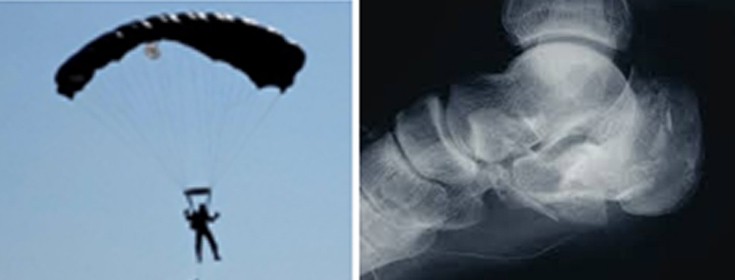

Τα κατάγματα του αστραγάλου ή της πτέρνας ονομάζονται «κάταγμα των αλεξιπτωτιστών», γιατί επισυμβαίνουν σε απότομη πτώση επί των ποδιών, από κάποιο ύψος.

Το κάταγμα του σώματος του αστραγάλου είναι αρκετά πιο σπάνιο από το κάταγμα της πτέρνας. Και τα δύο οστά είναι σπογγώδη, περισσότερο η πτέρνα, γι΄ αυτό όταν σπάσουν, μέρος του οστού εμβυθίζεται μέσα στο υπόλοιπο οστούν.